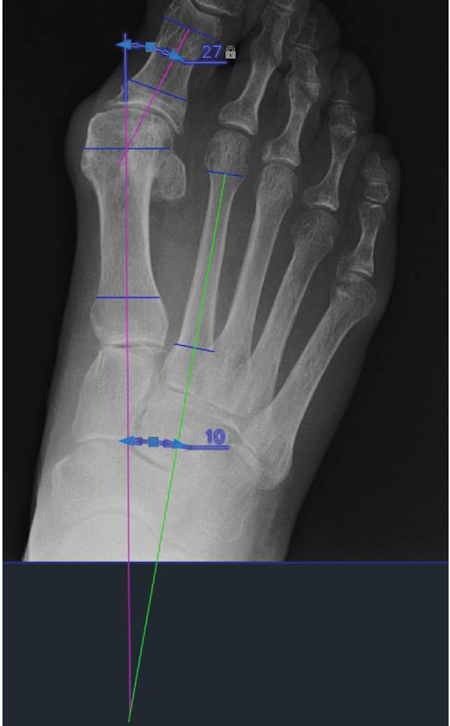

b) Mediciones radiográficas: Estas medidas son las realizadas en las radiografías dorsoplantares en carga prequirúrgicas y postquirúrgicas a los 6 meses.

El aparato de rayos utilizado es una unidad portátil de rayos X-Mind AC® con colimador. Los casettes utilizados han sido Kodak X-Omatic® de 18 x 24 cm con pantalla de intensificación regular y película de color azul, escogidos de este tamaño porque permiten la realización de una proyección dorsoplantar en carga del pie. Cada radiografía ha sido previamente digitalizada utilizando el escáner Epson Expression 1680 Pro®, con capacidad para explorar imágenes en films positivos. Una vez se obtiene la imagen radiográfica digital, se realizan las mediciones con el software AutoCAD® 2022 (Autodesk Inc, San Rafael, California, EE. UU.).

Como se observa en la Figura 3, los ángulos medidos en este estudio han sido: el ángulo hallux valgus o ángulo metatarso-falángico del primer dedo (AHV) y el ángulo intermetatarsal entre primer y segundo metatarsiano (AIM). Ambos ángulos han sido escogidos por ser los más empleados y relevantes para la valoración de la deformidad HAV.

Figura 3. Nuevo instrumento de medición de la movilidad del primer radio.

Respecto a los ángulos radiológicos, los resultados obtenidos mostraron diferencias significativas en ambos ángulos pre y postquirúrgicos. Dado que el AHV pasó de 30.92° ± 8.54° a 11.85° ± 3.85° y el AIM pasó de 12.77° ± 3.00° a 5.54° ± 1.80° tras la cirugía de HAV. Estos datos son similares a los reportados por otros autores que emplearon un periodo de seguimiento mayor19,23,26-28. Cabe destacar de nuevo a Coughlin y cols.19 por relacionar la variación de estos ángulos con la dorsiflexión del primer radio, aunque solo encontraron una correlación débil entre estas variables, en consonancia con los resultados del presente estudio.